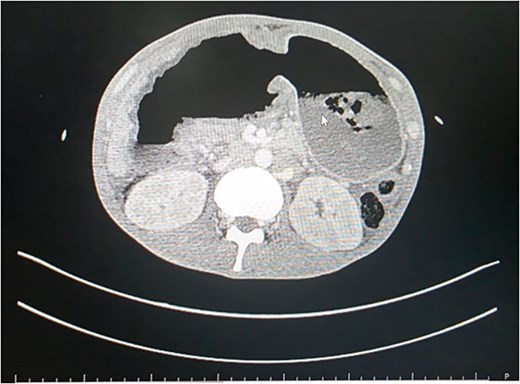

Blood tests revealed low hemoglobin levels (2.1gm/dl), decreased white blood cells (WBC) count (38 840/mm3) as well as serum albumin levels (2.09 mg/dl). Contract enhanced computed tomography (CECT) scan revealed markedly distended stomach with hour-glass configuration, non-enhancement of the distal portion of the stomach (Fig. 1) and proximal (D1 and portion of D2) duodenum. Non-opacification of the contrast in gastroduodenal artery was noted. Obliteration of the distal most portion of the superior mesenteric vein (70%) and non-enhancement of the pancreatic neck was appreciated. Hypoperfusion of the pancreatic head was evident with moderate ascites. Initially findings were thought to be a sequela of changes for gastric volvulus or pancreatitis.